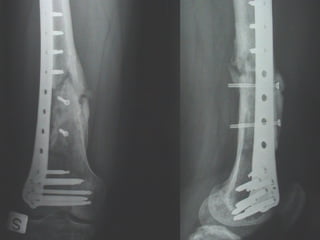

INDICAZIONI COMUNI Fratture sovracondiloidee Fratture intercondiliodee Fratture diafisarie distali PARTICOLARI Fratture con grave osteoporosi Fratture periprotesiche

VANTAGGI CHIRURGIA MININVASIVA Mini Open Inserimento della placca sottocutaneo per scivolamento Viti percutanee Preservazione dei tessuti molli Ridotto danno vascolare Rapida ripresa funzionale

F, 68 y

LISS  NCB

NCB

Conclusioni Riduzione  anatomica Minimo trauma chirurgico Corretto equilibrio fra elasticità e stabilità Precoce mobilizzazione